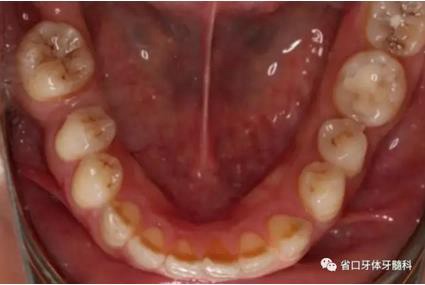

1.?病例簡(jiǎn)介 43歲女性患者,主拆:右上前牙松動(dòng)不適數(shù)日要求修復(fù)。現(xiàn)病史:患者數(shù)年前右上前牙因“齲壞”于外院行根管治療(具體不詳),數(shù)日前牙冠松動(dòng)不適,現(xiàn)覺(jué)影響咀嚼及美觀,遂來(lái)我院要求進(jìn)一步診治。否認(rèn)高血壓、心臟病等重大疾病,否認(rèn)結(jié)核、肝炎等傳染病史,否認(rèn)手 術(shù)、輸血史等,未發(fā)現(xiàn)藥物過(guò)敏。無(wú)吸煙習(xí)慣。臨床檢查:口外觀顏面基 本對(duì)稱,皮膚無(wú)紅腫破潰,顳下頜關(guān)節(jié)區(qū)無(wú)彈響、雜音、壓痛,開(kāi)口度約 37mm,開(kāi)口型“↓”,頜下、刻下和頸部未及腫大淋巴結(jié)。中位笑線??趦?nèi)檢查,口腔衛(wèi)生可,色素(+),BOP(-),PD=2mm,上頜右側(cè)中切 牙冠部變色,冠根折斷至齦下3mm,叩不適,松動(dòng)Ⅱ°~Ⅲ°。牙齦稍紅, 齦緣水平及齦乳頭高度可,屬于中厚齦生物型,附著齦寬度約5mm,唇系帶附著可。上頜右側(cè)中切牙缺牙間隙與對(duì)側(cè)同名牙一致,約>7mm,修復(fù)空 間良好。與對(duì)頜牙覆合覆蓋正常。MCT檢查示上頜右側(cè)中切牙冠根折斷至骨 下,根管內(nèi)見(jiàn)充填物,根充不全,根尖見(jiàn)陰影,大小約3mm×3mm。牙槽窩根方可用骨量可,唇側(cè)骨壁完整,冠方骨壁厚度約1mm。

圖2 術(shù)前口內(nèi)照

圖3 術(shù)前口內(nèi)照